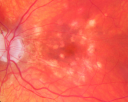

Bilateral Diffuse Uveal Melanocytic Proliferation - BDUMP - Paraneoplastic Syndrome822 views80-year-old man vision loss for one year. He died about one year after these photos from Metastatic Poorly Differentiated Large Cell Carcinoma of unknown primary. He was a smoker.